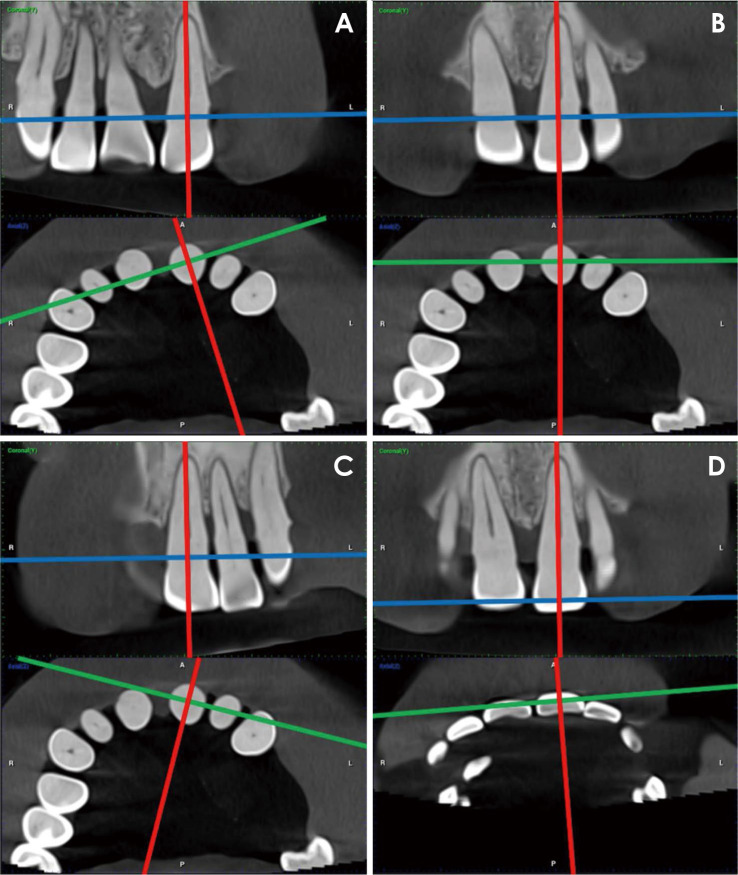

Purpose: This study was performed to introduce, evaluate, and compare various novel assessment protocols designed for straightforward, reliable, and reproducible measurement of alveolar bone levels. These protocols are intended for standardized periodontal assessment and follow-up, utilizing cone-beam computed tomography (CBCT) images and manipulation of Digital Imaging and Communications in Medicine (DICOM) viewer software.

Materials and methods: Two experienced oral and maxillofacial radiologists developed 5 distinct radiographic measurement protocols. These techniques were established to assess the alveolar bone level of a periodontally affected upper central incisor using a method that is consistently repeatable across observers. Two additional assessors, blinded to the details of the study, independently applied the protocols to retrieved DICOM files that met the eligibility criteria. A scoring system with 3 subscores was created and used to compare the protocols.

Results: Statistically excellent inter-observer reliability was observed for all protocols, other than protocol 1, which demonstrated moderate reliability. The average discrepancy between measurements taken by the 2 observers was 1.2 mm for protocol 1, 0.81 mm for protocol 2, and less than 0.5 mm for the remaining 3 protocols. All approaches except protocol 4 were straightforward to apply.

Conclusion: This study introduces multiple reliable protocols for the evaluation of periodontal bone levels that ensure consistency across observers. Based on the findings, the double axial lines and incisocrestal distance protocols are recommended. These new assessment approaches, along with any future modifications, may be useful in periodontal assessment, dental implant follow-up, orthodontic evaluation, research, and artificial intelligence model generation.